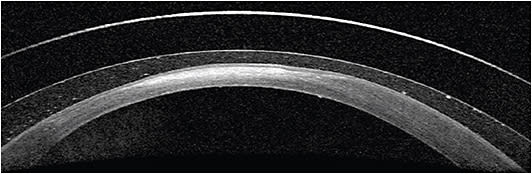

Scleral contact lenses are large in diameter and rest on the scleral surface, providing a vault over the corneal surface. This vault allows for a fluid cleft between the contact lens and cornea.

Specific subtypes of scleral contact lenses may be customized to fit the size and shape of varying irregularities of the ocular surface. These contact lenses offer ocular surface masking and support due to their significant vault.

Additionally, scleral contact lenses provide added patient comfort in some cases, as they do not rest directly on the corneal surface.